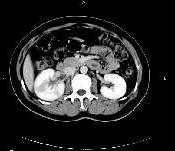

问题 女,27岁,寒战高热、尿频、尿痛3天,尿检:白细胞(+++),CT平扫及增强扫描如图所示,下列说法错误的是 ( )

选项 A、考虑为急性肾盂肾炎 B、考虑为慢性肾盂肾炎 C、增强后可见条片状密度减低区 D、左肾未见异常 E、右肾体积增大

答案 B